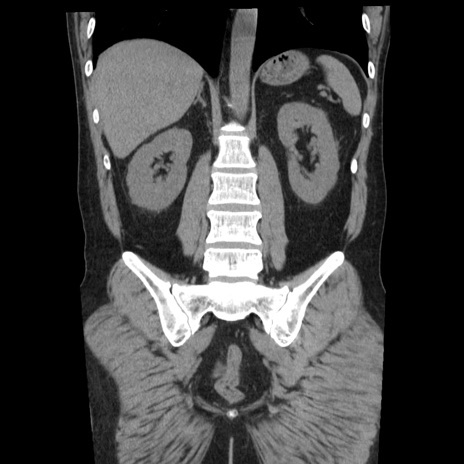

横断像

【症例】40歳代男性

【現病歴】2日前から胃痛あり。徐々に周期的な激痛に変化した。本日になっても激痛があるため受診。

【身体所見】意識清明、BT 38-39℃台あり、腹部:膨満、やや硬、右下腹部に圧痛あり。

【データ】WBC 8500、CRP 23.26